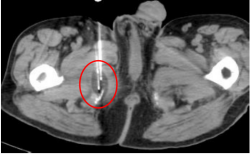

在手术实施过程中,医疗团队密切配合,在影像监测下完成相关操作。

术中情况

冷冻后,CT扫描显示冰球覆盖肿瘤,消融范围边界清晰。